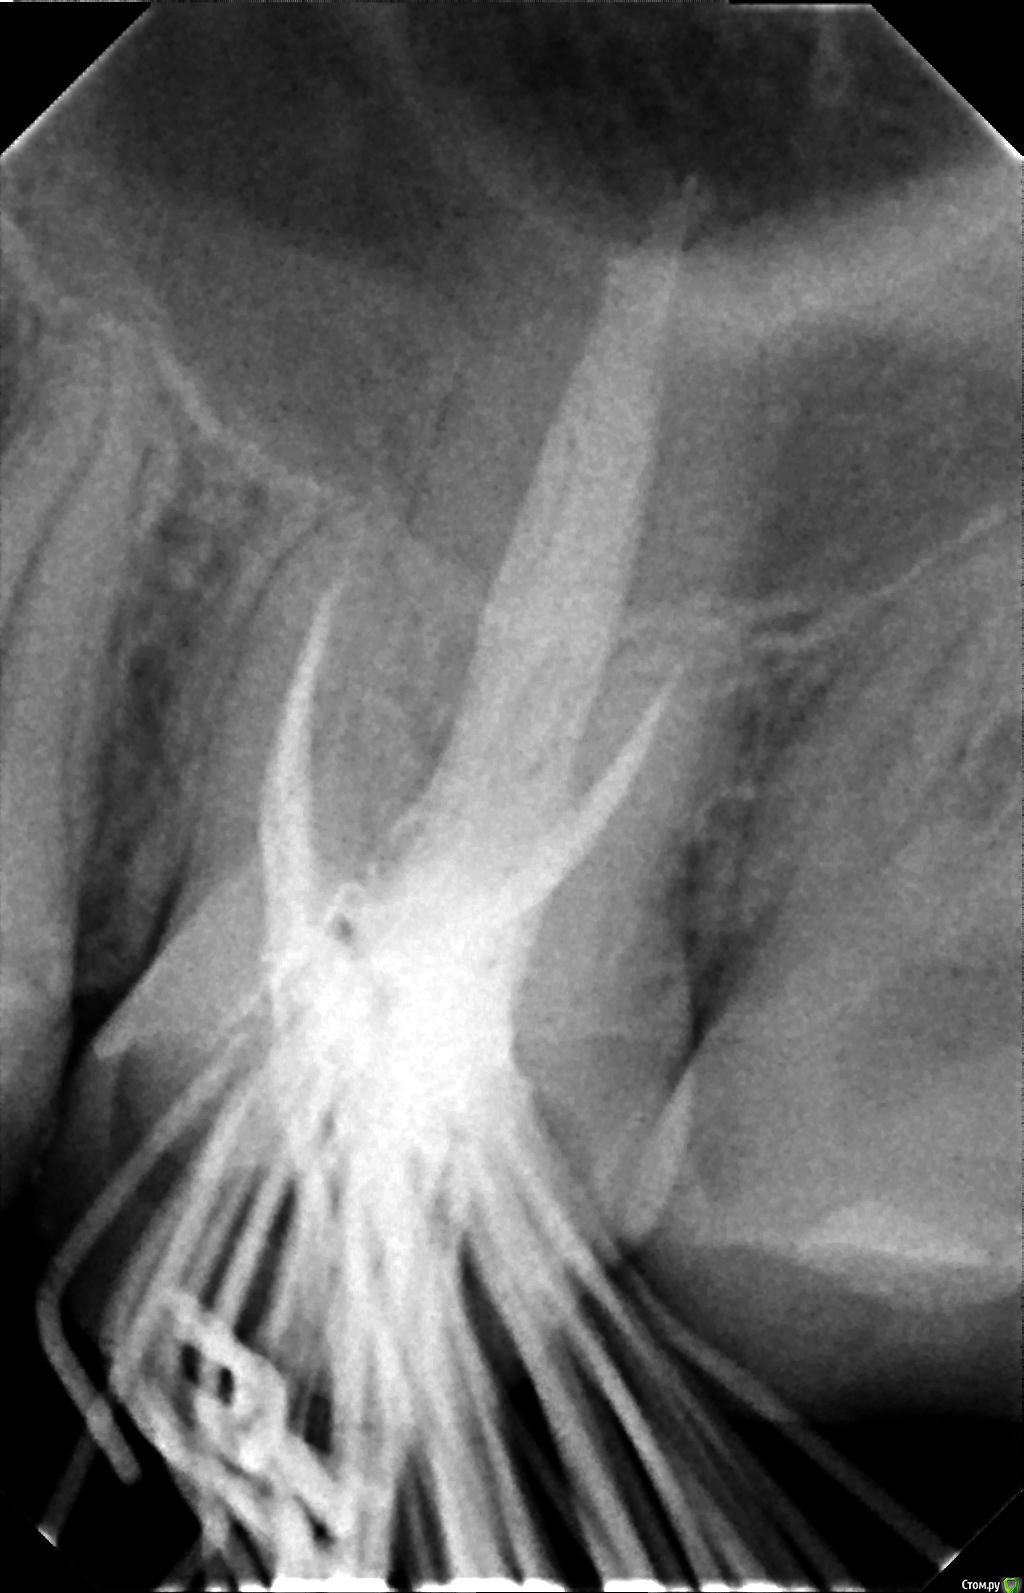

К сообщению прикреплены фотографии процесса лечения 26-го зуба.

После пломбировки каналов, я решил пойти ставить коронку в другую клинику, но там мне сказали, что не дают гарантию на этот зуб, поскольку каналы не долечены, и что я могу обратиться по гарантии в первую клинику. Но в первой клинике мне сказали, что все долечено. Хочу узнать мнение специалистов по этому поводу. Должен ли канал очищаться и пломбироваться до самой границы корня? Видно ли, что зуб не долечен по этим снимкам?

Так же в первой клинике в процессе лечения мне говорили, что у меня в зубе 5 каналов. Из-за этого цена лечения должна была быть еще дороже, но сказали, что мне оказали благосклонность и вылечили пятый канал бесплатно. В другой клинике мне сказали, что информация про 5-й канал - это ложь.